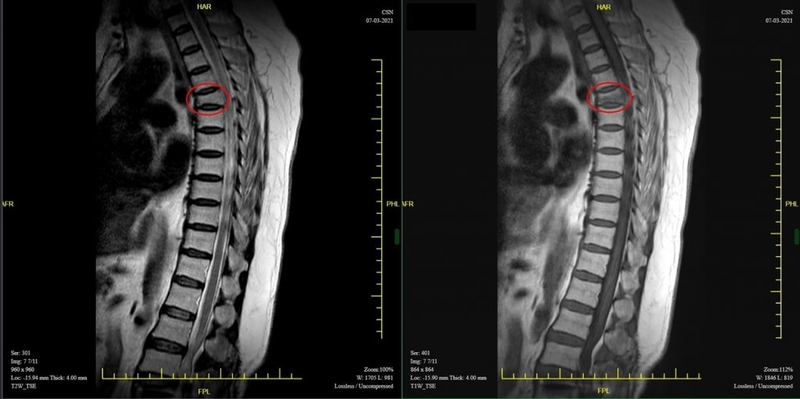

Việc chụp cộng hưởng từ sẽ giúp bác sĩ thấy được tủy sống, các rễ thần kinh, tình trạng phì đại, thoái hóa hay khối u để có chẩn đoán tốt nhất.

Cần dựa vào triệu chứng và các phương pháp cận lâm sàng để chẩn đoán xẹp đốt sống